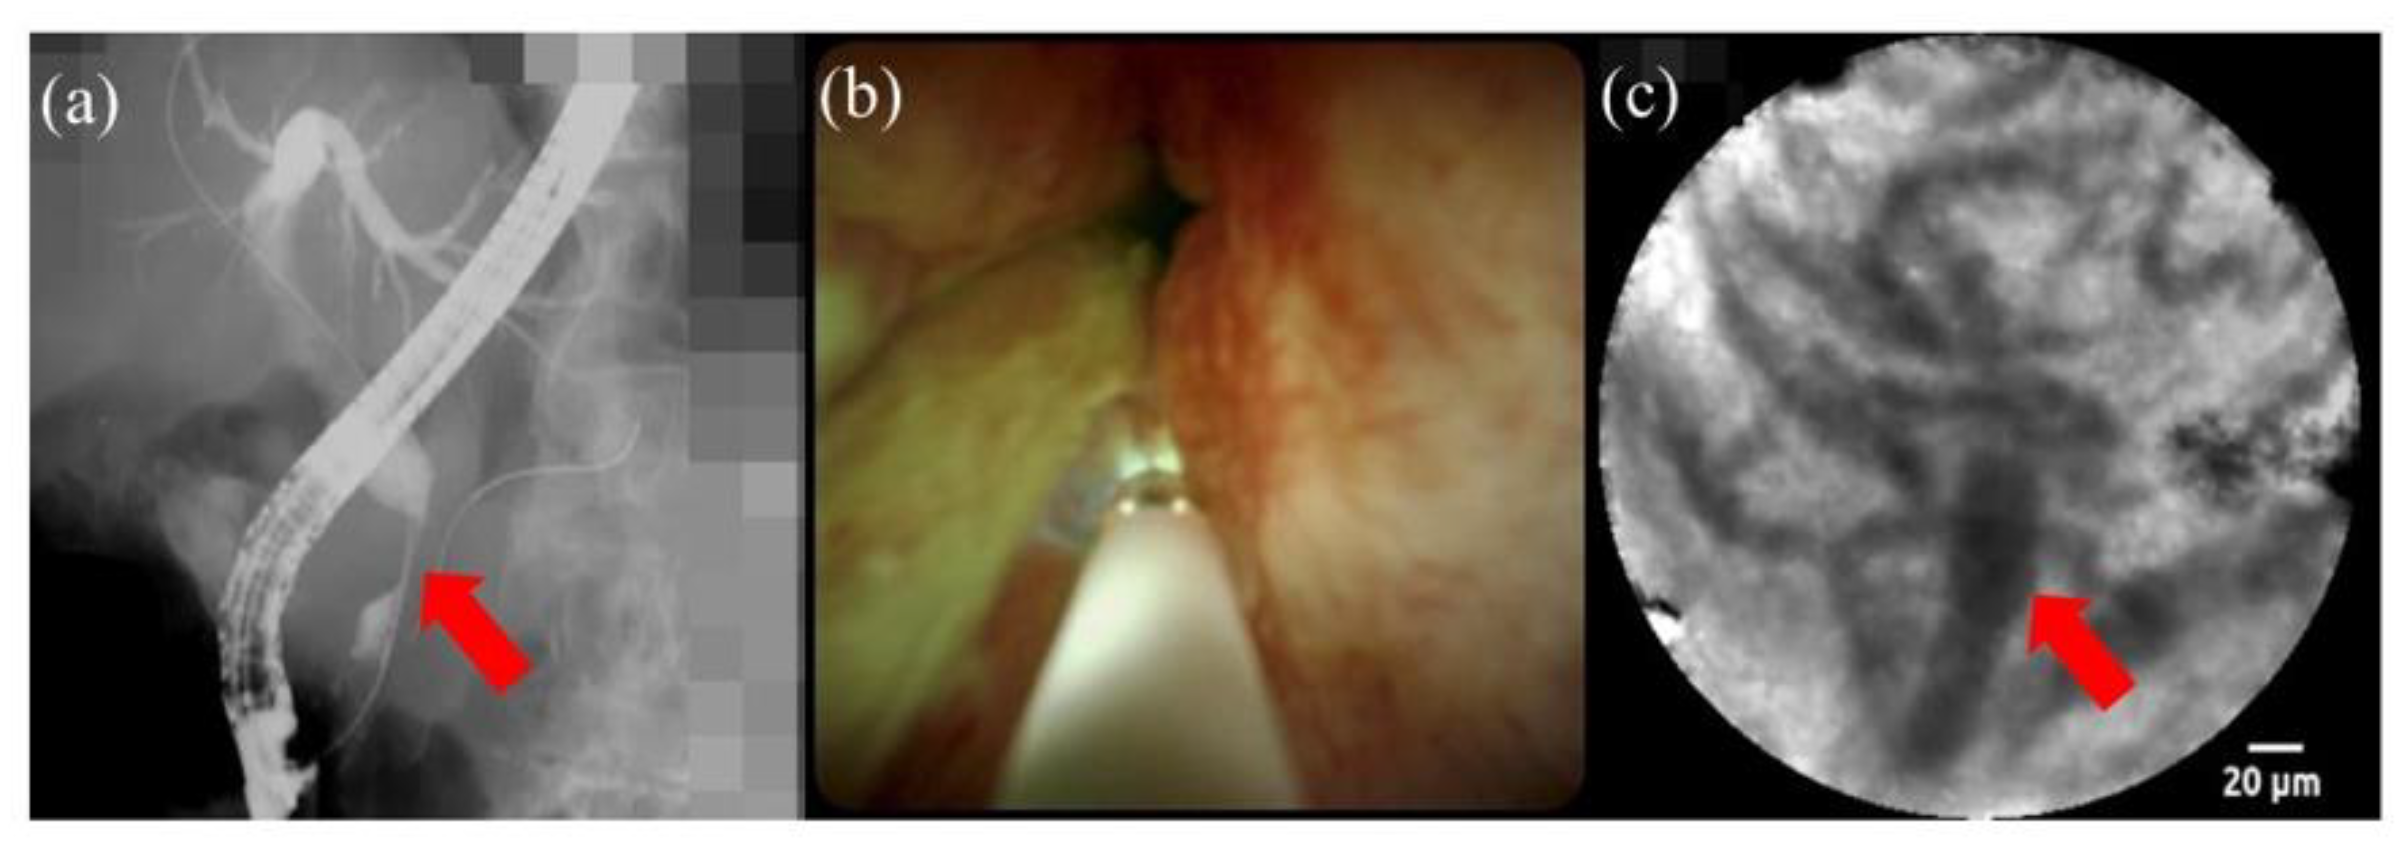

- Slivka, A.; Gan, I.; Jamidar, P.; Costamagna, G.; Cesaro, P.; Giovannini, M.; Caillol, F.; Kahaleh, M. Validation of the diagnostic accuracy of probe-based confocal laser endomicroscopy for the characterization of indeterminate biliary strictures: Results of a prospective multicenter international study. Gastrointest. Endosc. 2015, 81, 282–290. [Google Scholar] [CrossRef]

- Tanisaka, Y.; Ryozawa, S.; Nonaka, K.; Yasuda, M.; Fujita, A.; Ogawa, T.; Mizuide, M.; Tashima, T.; Araki, R. Diagnosis of biliary strictures using probe-based confocal laser endomicroscopy under the direct view of peroral cholangioscopy: Results of a prospective study (with video). Gastroenterol. Res. Pract. 2020, 2020. [Google Scholar] [CrossRef] [PubMed]